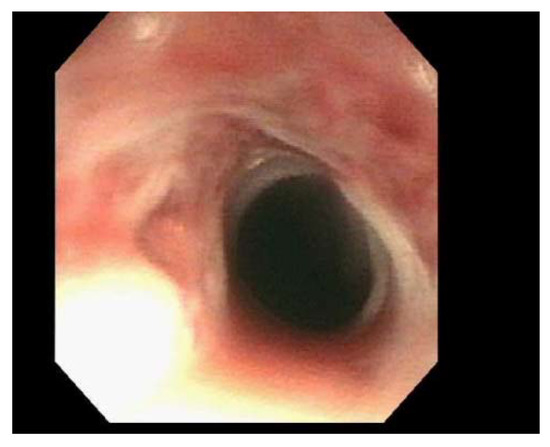

| Patient 1 | Single benign appearing intrinsic stenosis located 15 mm from the UES dilated with a TTS balloon dilator to 20 mm, gastric mucosal atrophy |

| Patient 2 | Web/stenosis at the cricopharyngeus unable to pass with neonatal scope due to resistance, guideware placed under fluoroscopic guidance and dilation performed with Savary dilator to 8 mm |

| Patient 3 | Two benign appearing intrinsic stenoses were found at the circopharyngeus at 15 cm and 20 cm from the incisors that could not be traversed with the neonatal scope, dilation performed with Savary dilators to 11 mm |